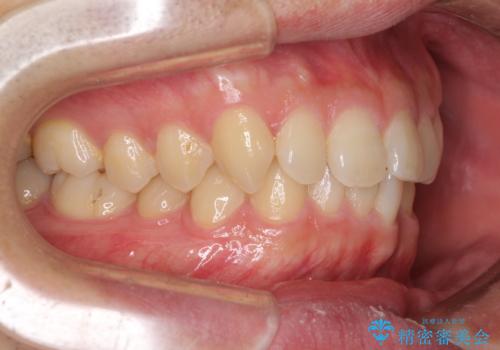

前歯の咬み合わせとデコボコを解消 インビザラインによる矯正治療

- 上下前歯のデコボコと深い咬み合わせを気にして来院された患者様です。

インビザラインによる上下歯列の拡大と、IPR(歯と歯の間を削る)にるスペースの獲得により、前歯のデコボコとディープバイトを改善することとしました。

もう少し下の前歯を整えたかったのですが、患者様の治療を早く終了させたいという希望により、細かい叢生を残しての終了となりました。